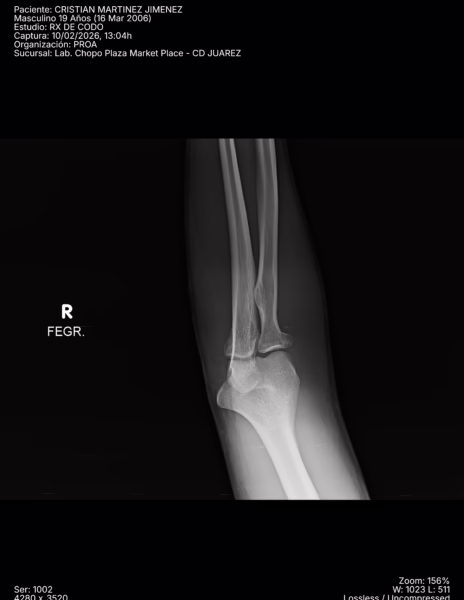

RADIOGRAFIAS AP Y LATERAL DE CODO

LAS PROYECCIONES RADIOLOGICAS OBTENIDAS NOS MUESTRA LOS SIGUIENTES HALLAZGOS:

-Tejidos blandos, a nivel de fosa de codo con aumento la densidad y grosor..

-Almohadilla grasa anterior, con el signo de la vela.

-Radio, con pérdida de la contigüidad a nivel de cabeza que involucra la porción medial, no desplazada. Resto de lo valorado de radio y cubito, sin evidencia de lesiones líticas, blásticas o perdida de la contigüidad.

-De lo valorado de humero, sin evidencia de lesiones líticas, blásticas o perdida de la contigüidad.

-Espacios articulares observados, sin evidencia alteraciones.

OPINIÓN RADIOLÓGICA:

− EN EL PRESENTE ESTUDIO RADIOGRÁFICO, EXISTE FRACTURA A NIVEL DE CABEZA DEL RADIO DE PREDOMINIO MEDIAL CON EDEMA ASOCIADO E INVOLUCRO ARTICULAR (HEMARTROSIS).